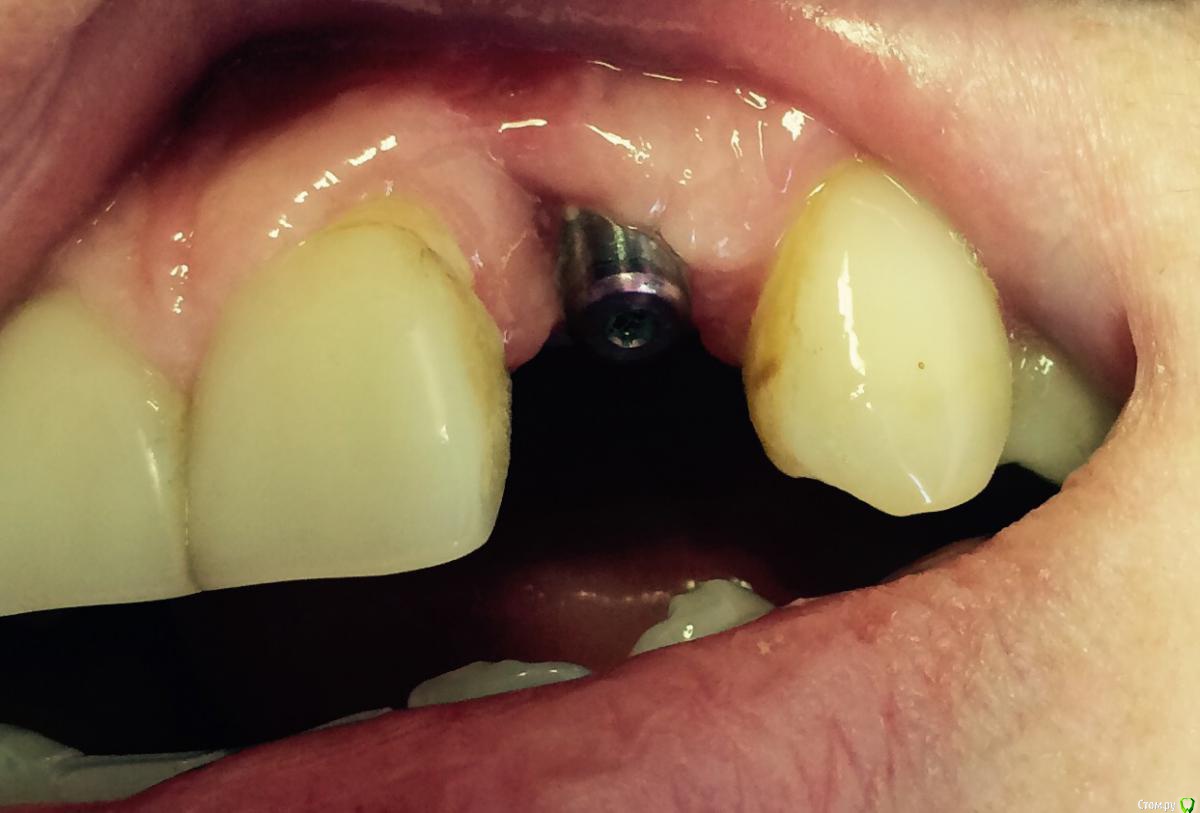

Kitty82 Опубликовано 15 сентября, 2015 Поделиться Опубликовано 15 сентября, 2015 Вот такая неудача. Пациентка непростая, начинали с ламины, на этапе и имплантации и установки формирователя подсадка ССТ с бугров, но каждый раз ССТ убирала вместе с гноем. Никак не хотят у нее приживаться ССТ, хотя все делала то же самое, что у других. Как занозы мешают заживлению. Связываю и гипотиреозом, но пациентка утверждает, что под постоянным наблюдением эндокринолога, на гормонах. Результат, конечно, пациентку не устраивает. Боюсь, что третья подсадка так же закончится неудачей. Хочу VIP-CT, но смущает усадка отдаленно и тощее нёбо. Может что порекомендуете. Рецессию на 21 VIP не закроет? Ссылка на комментарий

Kitty82 Опубликовано 15 сентября, 2015 Автор Поделиться Опубликовано 15 сентября, 2015 снимок на этапе установки формирователя десны. 4 недели назад Ссылка на комментарий